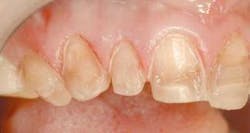

The final result of this case sees an improvement in all of the original objectives (Figs. 12, 13, 14). Our patient wanted a lighter, wider smile that would cover the darkness she had lived with her entire life. Needless to say, she was ecstatic with the end results (Figs. 15, 16).

null